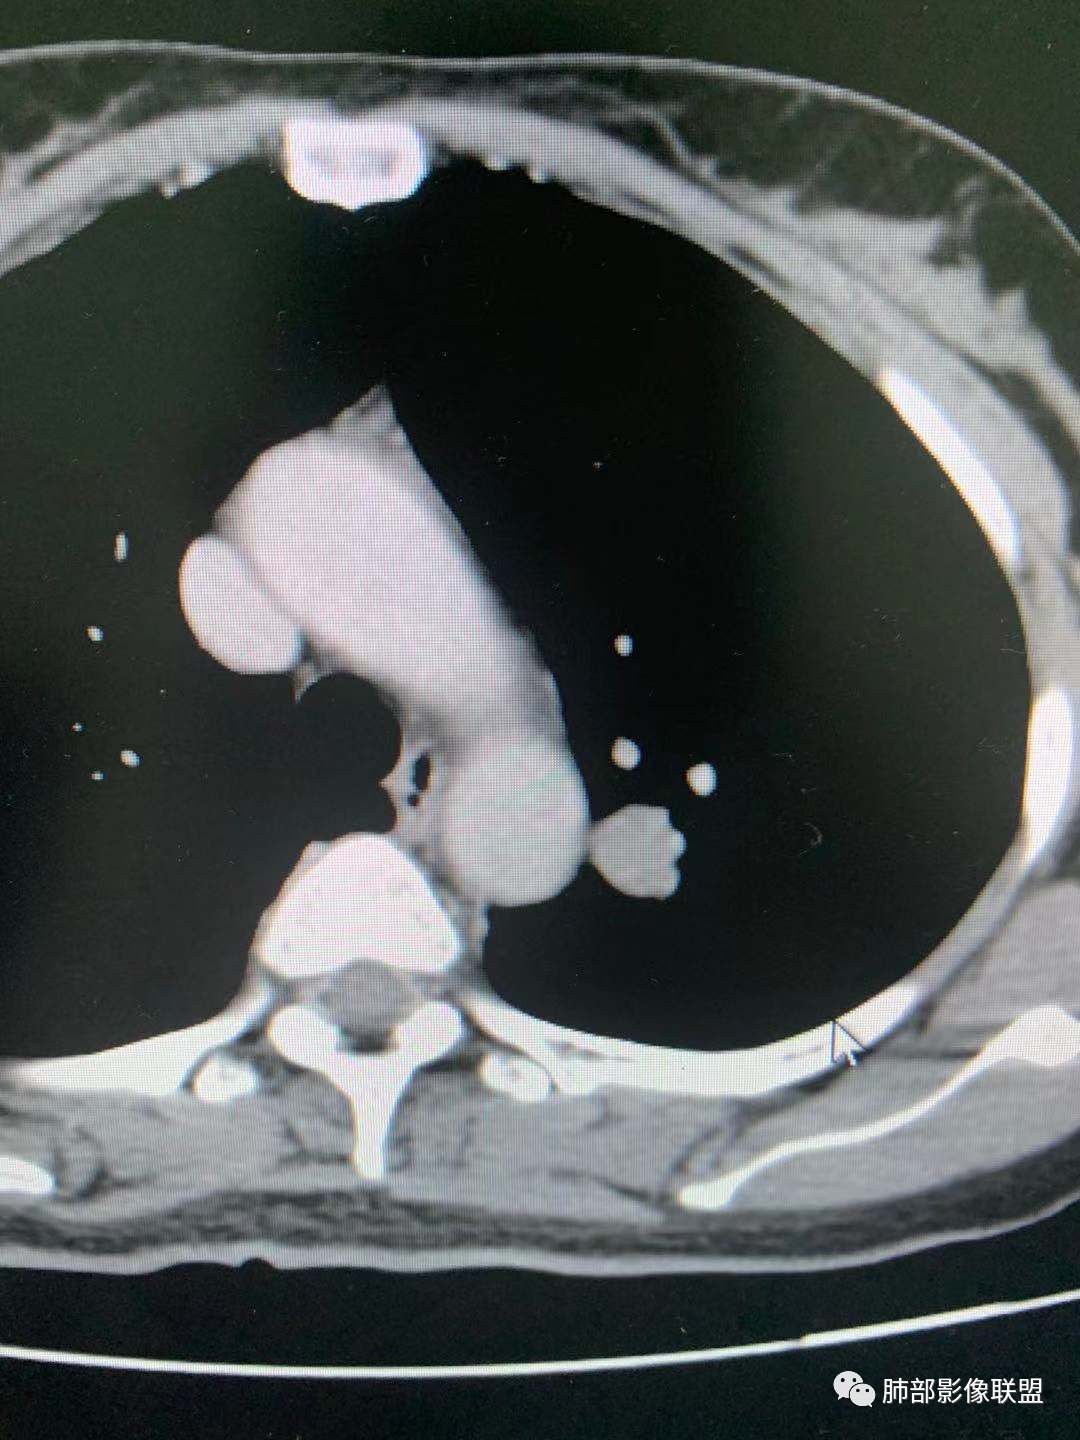

左肺上叶实性结节,边缘光滑清晰,血管贴边,渐进性延迟强化,密度均匀,考虑PSP.

贴边血管征,强化延迟,考虑PSP

左肺上叶实性结节,边缘光滑清晰,血管贴边,渐进性延迟强化,密度均匀,考虑PSP.但是强化幅度不够,需要鉴别早期肺癌 医学百科网 | YxBaike.Com

最大的靠后,有血管贴边征,渐进性明显强化,考虑PSP可能大

首先考虑PSP,周围可疑磨玻璃,鉴别恶性病变 医学百科网 | YxBaike.Com

中年女性,左肺上叶实性圆形结节,边缘有晕,血管及支气管贴边,强化尚均匀,渐进性明显强化,考虑为PSP可能